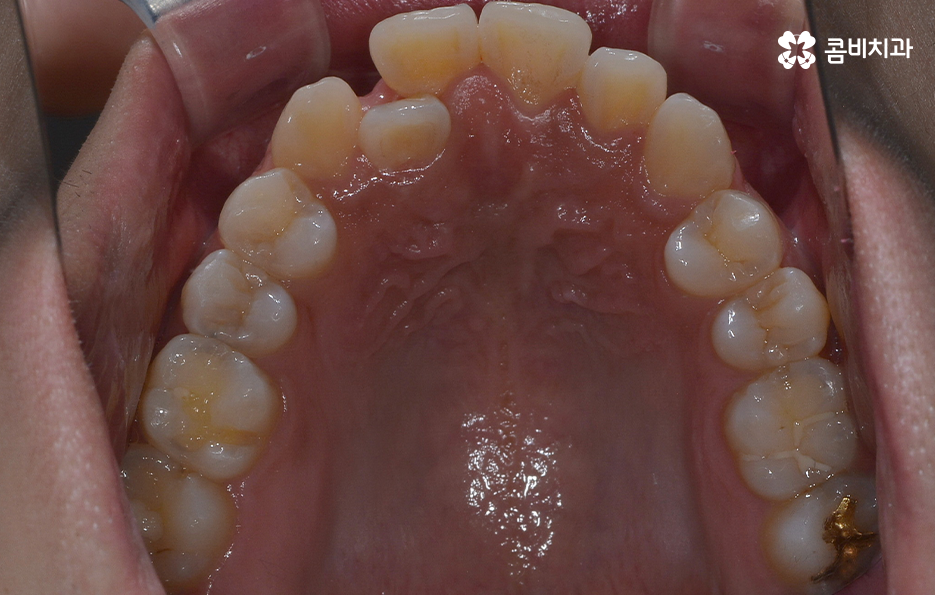

덧니의 주된 원인이 턱뼈가 좁아서 치아가 자랄 공간이 부족하다 보니 덧니의 형태로 영구치가 자라는 경우가 많다 보니 전체 치열을 가지런하게 재배열 하기 위해서는 충분한 치아의 이동 공간이 필요하고 치아의 이동 공간을 확보하는 방법으로 주로 소구치 즉 작은 어금니를 발치하는 발치교정 방식이 보편적으로 많이 활용되고 있는데요

치아교정을 위한 발치교정 과정은 대부분 소구치 라고 불리는 첫번째 작은 어금니를 발치하게 되며 좌우, 위 아래 총 4개의 소구치를 발치한 후에 덧니가 재배열 될 수 있는 공간을 만들기 위하여 우선 송곳니를 후방으로 이동시키고 있어요

그 다음으로는 송곳니가 후방으로 이동하면서 확보된 공간으로 앞니의 배열을 가지런하게 맞추고 있는데요. 앞니의 재배열과 함께 발치 교정으로 인해 빈 공간이 발생한 부분을 없애고 전체적인 치열을 미세하게 조절하게 되는데 발치교정은 치아의 움직임이 많은 편이기 때문에 교합이 잘 맞도록 마무리 배열을 잘해야 하며 그와 함께 치아가 많이 움직이는 만큼 얼굴형의 변화와 입술라인 등의 변화가 클 수 있다는 점에서 치료 후 결과를 잘 예측하여 처음 치료 계획부터 마무리까지 섬세하게 진행하실 필요가 있어요